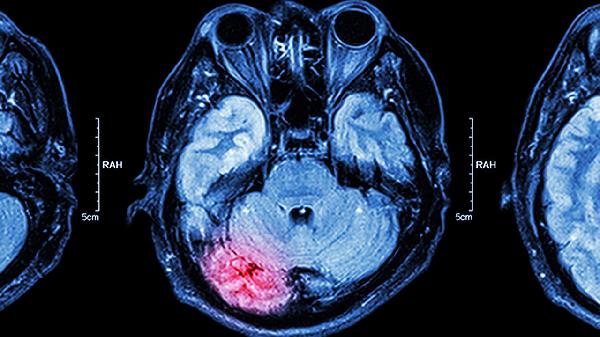

磁共振成像对软组织分辨率更高,能更敏感地发现早期脑癌,尤其是多模态MRI可鉴别肿瘤性质。PET-CT可评估肿瘤代谢活性,辅助判断良恶性。脑脊液检查对某些脑膜癌病有诊断价值。立体定向活检是确诊脑癌的金标准,通过病理分析明确肿瘤类型与分级。对于疑似脑癌患者,医生会根据临床表现综合选择检查手段。

出现持续头痛、癫痫发作、性格改变等神经系统症状时,应及时就医完善检查。确诊脑癌后需根据病理类型制定手术、放疗或化疗等个体化方案。日常应避免头部外伤,保持规律作息,高危人群可定期进行脑部筛查。